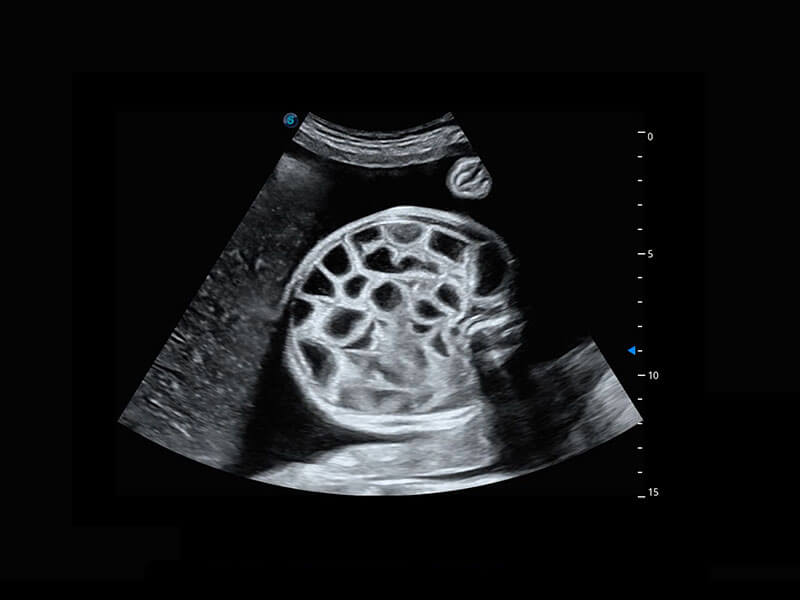

P60搭載一系列胎兒心臟成像技術(shù),實現(xiàn)精細的胎兒心臟評估。

四腔切面

胎心容積成像